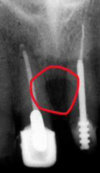

Perfectly

8

Q

what factors result in a foreshortened image?